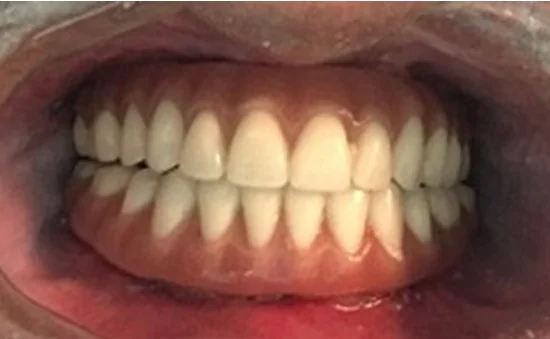

Paciente do sexo masculino, 51 anos, foi encaminhado ao Centro de Treinamento da DSp (Campo Largo, PR) com extrema mobilidade do incisivo superior esquerdo. O exame clínico evidenciou prótese dentária sem estabilidade devido à fratura de um remanescente dentário que serviu de auxílio adicional para este tipo de restauração. Foi sugerida a extração da raiz do dente remanescente e a instalação imediata do implante por meio da CN. Além disso, o preenchimento do GAP com biomaterial para manutenção do contorno gengival e restauração estética também foi planejado.

A cirurgia navegada para a instalação de implantes dentários em regiões estéticas é uma excelente alternativa para evitar resultados indesejados quanto à angulação do implante, melhorando sua precisão e reabilitação protética.